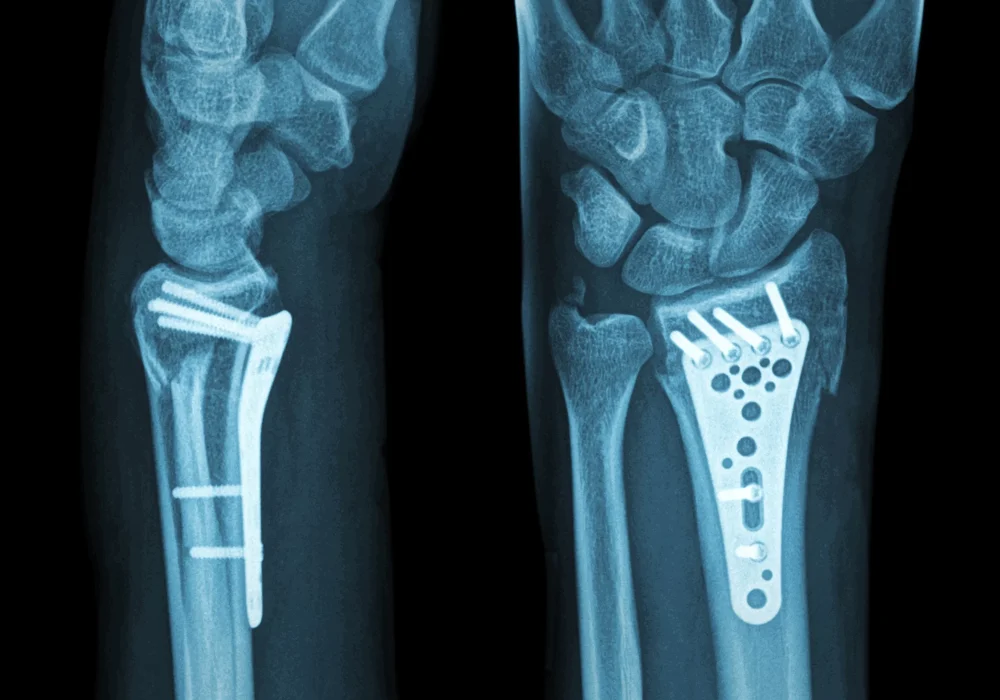

Distal radius plating

Distal radius plating is a surgical technique used to stabilize fractures of the distal radius using metal plates and screws. This method provides rigid fixation, allowing for early mobilization and improved anatomical alignment of the fractured bone fragments. The plates are typically made of stainless steel or titanium, designed to contour to the shape of the distal radius.

Volar locking plates are the most commonly used implants for distal radius fractures. They are applied to the volar (palm) side of the radius and have locking screw technology that provides angular stability. This is especially beneficial in osteoporotic bone where screw purchase may be compromised.

4. Plate Application: The selected plate is contoured and positioned on the bone. Screws are inserted to secure the plate and maintain fracture reduction.

5. Verification: Intraoperative imaging confirms proper alignment and hardware placement.